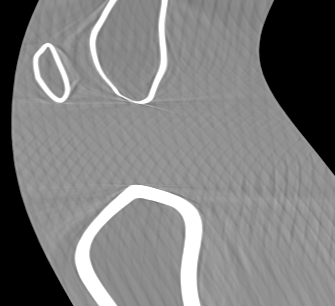

Involuntary subject motion is the main source of artifacts in weight-bearing cone-beam CT of the knee. To achieve image quality for clinical diagnosis, the motion needs to be compensated. We propose to use inertial measurement units (IMUs) attached to the leg for motion estimation. We perform a simulation study using real motion recorded with an optical tracking system. Three IMU-based correction approaches are evaluated, namely rigid motion correction, non-rigid 2D projection deformation and non-rigid 3D dynamic reconstruction. We present an initialization process based on the system geometry. With an IMU noise simulation, we investigate the applicability of the proposed methods in real applications. All proposed IMU-based approaches correct motion at least as good as a state-of-the-art marker-based approach. The structural similarity index and the root mean squared error between motion-free and motion corrected volumes are improved by 24-35% and 78-85%, respectively, compared with the uncorrected case. The noise analysis shows that the noise levels of commercially available IMUs need to be improved by a factor of $10^5$ which is currently only achieved by specialized hardware not robust enough for the application. The presented study confirms the feasibility of this novel approach and defines improvements necessary for a real application.